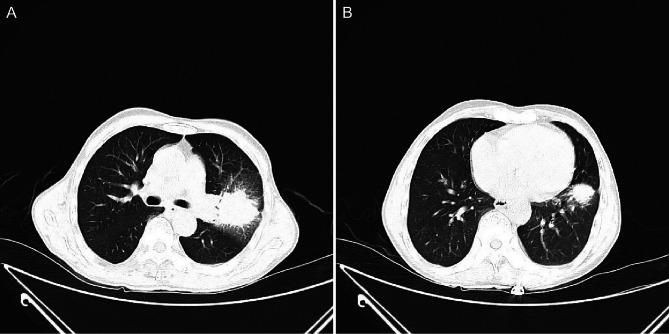

A 66-year-old man presented with cough, sputum, chest tightness and weight loss persisting for 1 month. Chest X-ray revealed a space-occupying lesion in the left lung. Further CT imaging demonstrated irregular soft tissue masses in both the upper and lower lobes of the left lung. Although the imaging findings suggested lung cancer, the final pathological diagnosis confirmed AFOP. The patient was treated with methylprednisolone, resulting in substantial improvement of the upper lobe lesion, whereas the lower lobe lesion showed minimal response. Following the addition of mycophenolate mofetil, the lower lobe lesion decreased substantially. Multiple lung biopsies confirmed the diagnosis of AFOP, with no evidence of a malignant tumour.

一名66岁男性,出现咳嗽、咳痰、胸闷和体重减轻症状持续1个月。胸部X线显示左肺有占位性病变。进一步的CT成像显示左肺上叶和下叶均有不规则软组织肿块。尽管影像学表现提示肺癌,但最终病理诊断确诊为AFOP。患者接受甲泼尼龙治疗后,上叶病变有显著改善,而下叶病变反应极小。加用霉酚酸酯后,下叶病变明显缩小。多次肺活检确诊为AFOP,无恶性肿瘤证据。